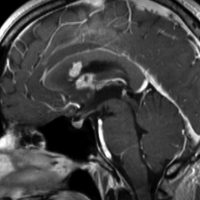

ガドリニウム増強では,前頭葉腫瘍というより,側脳室壁にベトベトくっついているような腫瘍です。germinoma特有のsubependymal infiltration像を示します。

左はICE化学療法 (IFO/CDDP/VP-16)前,右は1コース終了後です。腫瘍は顕著に縮小してgerminomaとして普通の化学療法反応性を示します。また,松果体と下垂体には腫瘍はありません。